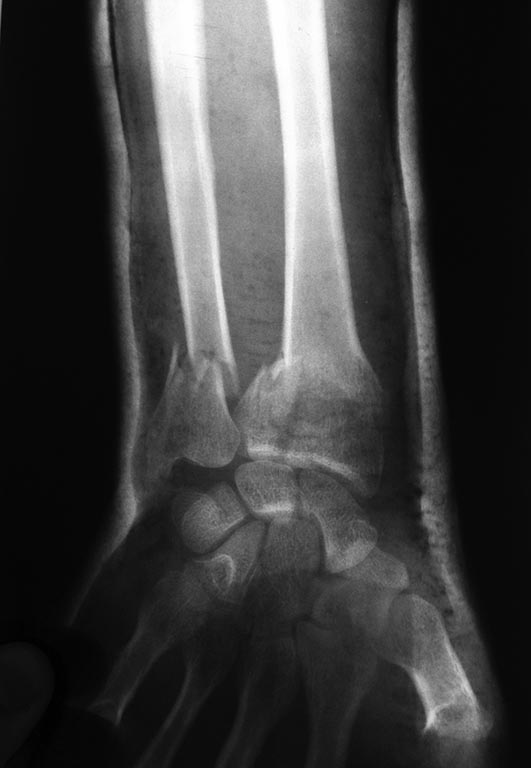

Здравствуйте, Александр Николаевич! Такой вариант я, находясь у Вас на учебе, видел и рассматривал. Но у меня перелом лучевой кости внутрисуставной и локтевая сломана. В итоге то, что придумалось мне показалось приемлемее.

Р-грамма после репозиции.